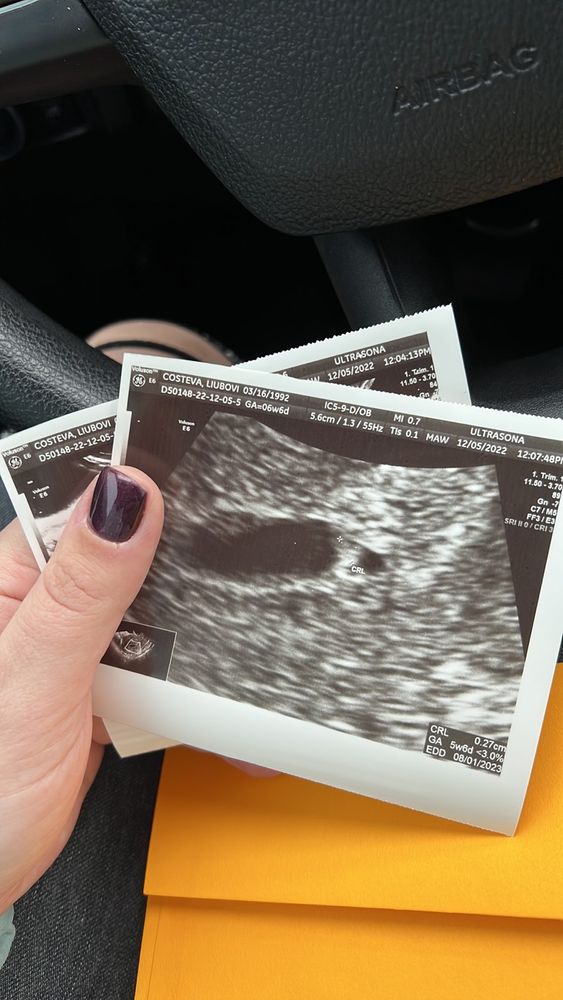

Перенос эмбриона. Нет сердцебиения.

Скорее всего у вас анембриония, на таком сроке правда уже было бы видно и эмбрион и сердечко У меня в 6+4 уже было сердечко

Наверное очень печально но это анембриония. К 6 неделям уже сб+ ... Пересдайте контрольное узи...

Tatyana, спасибо. Еще сделаю узи. Но на таком сроке как у меня должно биться сердце и очень хорошо биться. Поэтому я мало верю в положительный исход